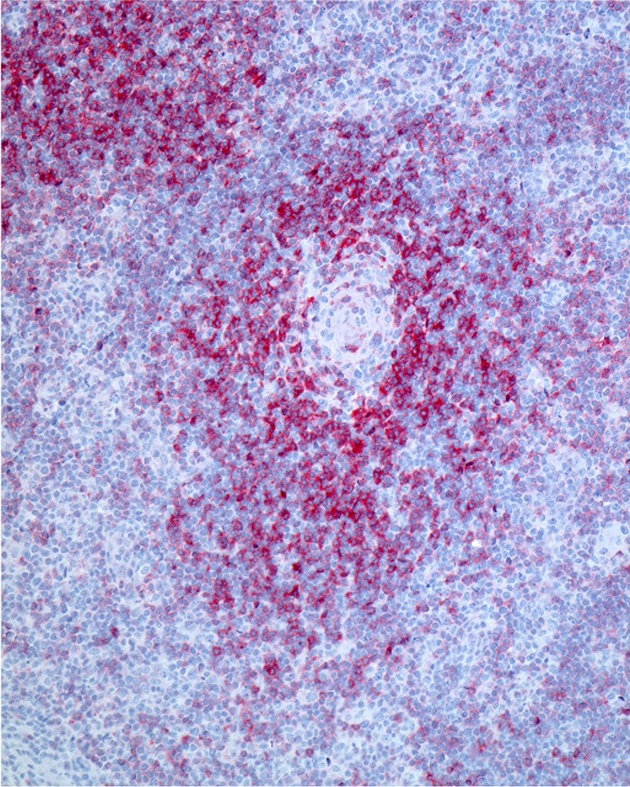

Im Bild: Die Mikroskop-Aufnahme zeigt die Anfärbung eines PD1-Oberflächenmoleküls auf Zellen eines angioimmunoblastischen T-Zell-Lymphoms (AITL). PD1 ist ein Molekül, das die körpereigene Immunabwehr hemmt. (Bildrechte: Prof. Dr. Sylvia Hartmann)